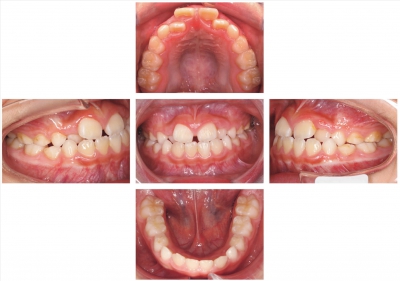

8歳の男児。前歯部の咬み合わせの異常を主訴として来院した。家族に同様の咬み合わせはいないという。他に特記すべき病歴はない。初診時の顔面写真と口腔内写真を別に示す。セファロ分析の結果を図に示す。

矯正治療に用いるのはどれか。2つ選べ。

a. チンキャップ

b. バイオネーター

c. リップバンパー

d. クワドヘリックス

e. 上顎前方牽引装置